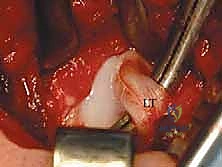

الخطوة 2: الشق الجراحي الدقيق (The Incision)

يقوم الدكتور هطيف بعمل شق عرضي أو طولي صغير (حوالي 3-4 سم) في الجهة الداخلية للفخذ، في منطقة الثنية المغبنية (Groin crease). هذا الشق تجميلي ومخفي تقريباً.

الخطوة 3: تسليخ الأنسجة والوصول إلى العضلات (Dissection)

بحرص شديد لتجنب الأوعية الدموية والأعصاب الحيوية (مثل الحزمة الوعائية العصبية الفخذية والعصب السدادي)، يتم إبعاد العضلات المقربة (Adductor muscles). في بعض الحالات، يتم تحرير (قطع جزئي) لوتر العضلة المقربة الطويلة (Adductor Longus) لتخفيف الشد على المفصل.

الخطوة 4: تحرير وتر العضلة الحرقفية القطنية (Psoas Tendon Release)

هذا هو أحد أهم أجزاء العملية. وتر العضلة الحرقفية القطنية يكون مشدوداً جداً في حالات DDH ويشكل حاجزاً يمنع رأس الفخذ من النزول إلى مكانه. يقوم الدكتور هطيف بعزل هذا الوتر وقطعه بدقة، مما يزيل الضغط الفوري عن المفصل.

الخطوة 5: فتح الكبسولة المفصلية (Capsulotomy)

بمجرد إزاحة الوتر، تظهر الكبسولة المفصلية بوضوح. يتم إجراء شق دقيق في الكبسولة (غالباً على شكل حرف T أو H) للوصول إلى داخل المفصل.

الخطوة 6: تنظيف التجويف الحقي (Clearing the Acetabulum)

الآن، يرى الجراح داخل المفصل. هنا تبرز الخبرة في إزالة العوائق الداخلية:

* يتم استئصال الرباط المدور (Ligamentum Teres) المتضخم الذي يشغل حيزاً كبيراً.

* يتم إزالة الأنسجة الليفية والدهنية المعروفة باسم البولفينار (Pulvinar).

* يتم شق الرباط الحقي المستعرض (Transverse Acetabular Ligament) إذا كان ضيقاً ويمنع دخول رأس الفخذ.

الخطوة 7: الرد الفعلي للمفصل (Reduction)

بعد تنظيف التجويف تماماً، يقوم الدكتور هطيف بتوجيه رأس عظم الفخذ بلطف شديد ليدخل ويستقر بعمق داخل التجويف الحقي. يجب أن يكون الرد مستقراً وسلساً دون الحاجة إلى قوة مفرطة. يتم فحص استقرار المفصل في وضعيات مختلفة للتأكد من عدم خروجه مرة أخرى.